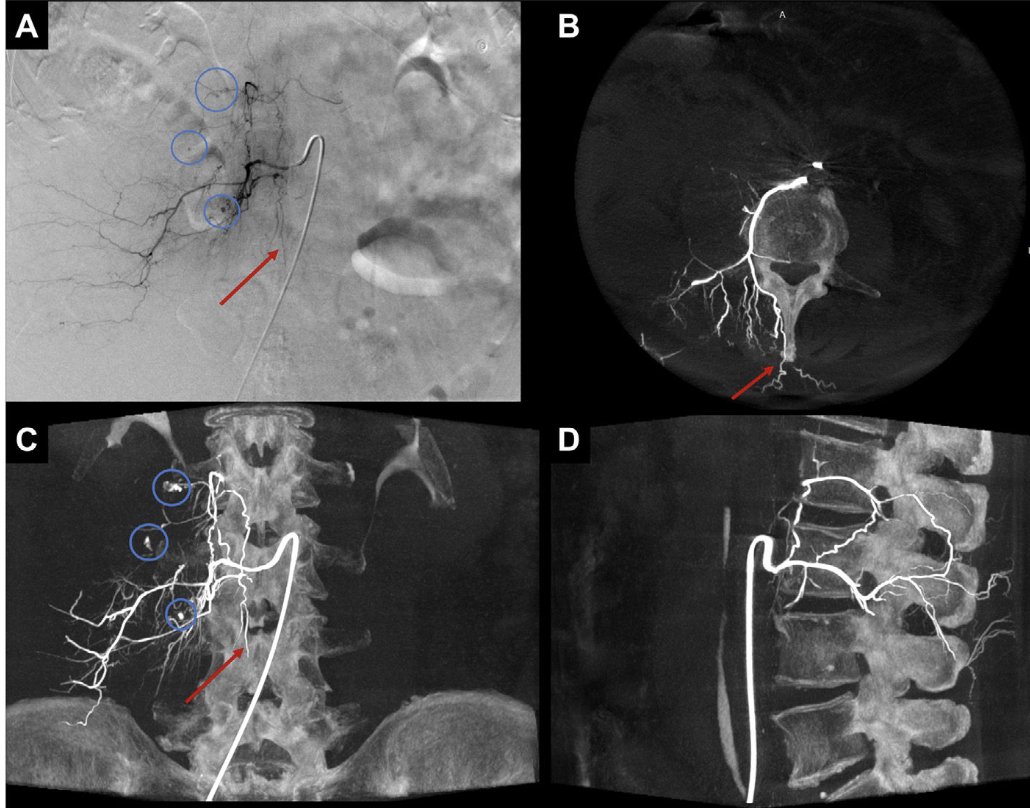

Y Radiología en imágenes presenta tres interesantes revisiones sobre las fístulas arteriales intraabdominales, el tumor desmoide y causas de fallo del implante coclear